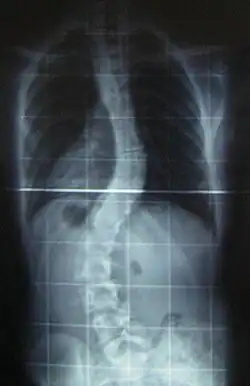

When scoliosis is suspected, weight-bearing, full-spine AP/coronal (front-back view) and lateral/sagittal (side view) X-rays are usually taken to assess the scoliosis curves and the kyphosis and lordosis, as these can also be affected in individuals with scoliosis. Full-length standing spine X-rays are the standard method for evaluating the severity and progression of scoliosis, and whether it is congenital or idiopathic in nature. In growing individuals, serial radiographs are obtained at 3- to 12-month intervals to follow curve progression, and, in some instances, MRI investigation is warranted to look at the spinal cord.[80] An average scoliosis patient has been in contact with around 50–300 mGy of radiation due to these radiographs during this period.[81]

The standard method for assessing the curvature quantitatively is measuring the Cobb angle, which is the angle between two lines, drawn perpendicular to the upper endplate of the uppermost vertebra involved and the lower endplate of the lowest vertebra involved. For people with two curves, Cobb angles are followed for both curves. In some people, lateral-bending X-rays are obtained to assess the flexibility of the curves or the primary and compensatory curves.[82][83]